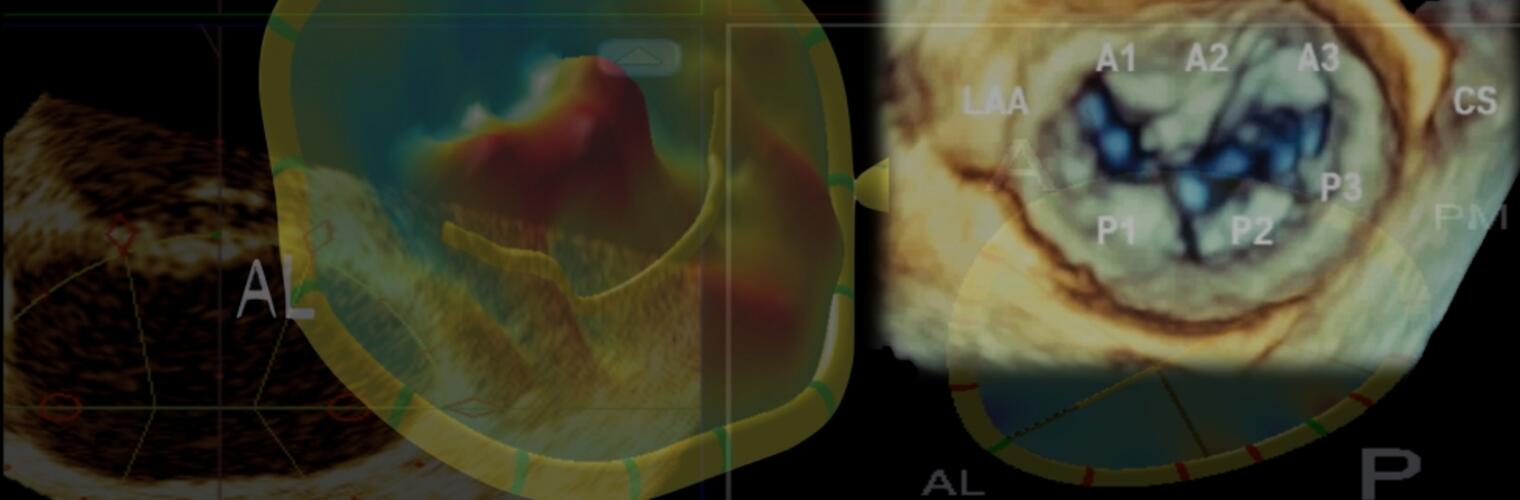

Echocardiography Derived 3D Printing

Quantitative Geometric Analyses

Boston Structural Heart Videos

Watch videos on cutting-edge technology and high-quality educational videos on echocardiography